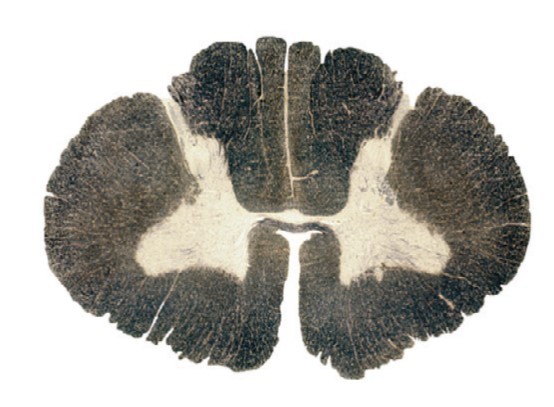

What is the correct order of spinal cord sections from cranial to caudal?

1, 3, 2, 4